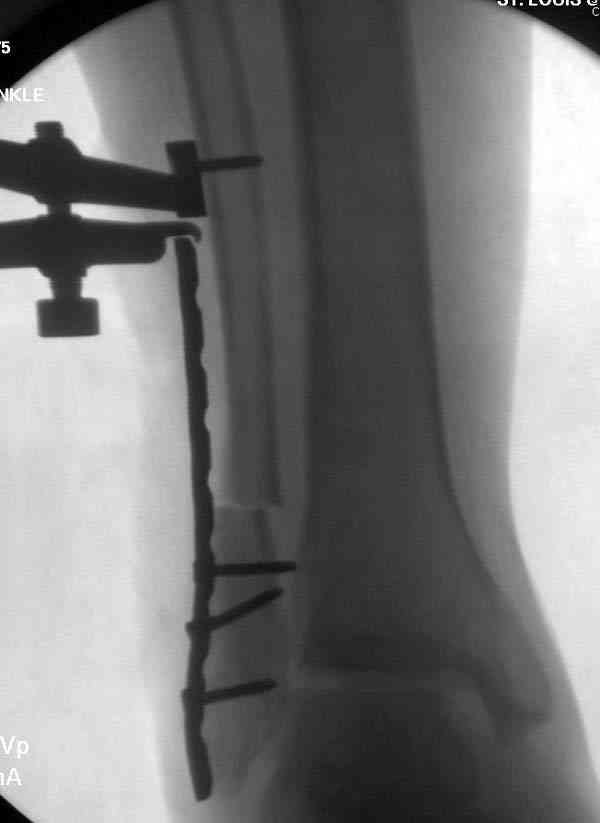

Проведена обычная стандартная процедура по исправлению неудовлетворительного состояния голеностопного сустава, где кроме удлинения малоберцовой с применением compression tension device за проксимальный конец пластины, проведено замещение трикортикальным графтом из крыла, освобождение синдесмоза и медиальной щели от

фибротических масс с фиксацией.